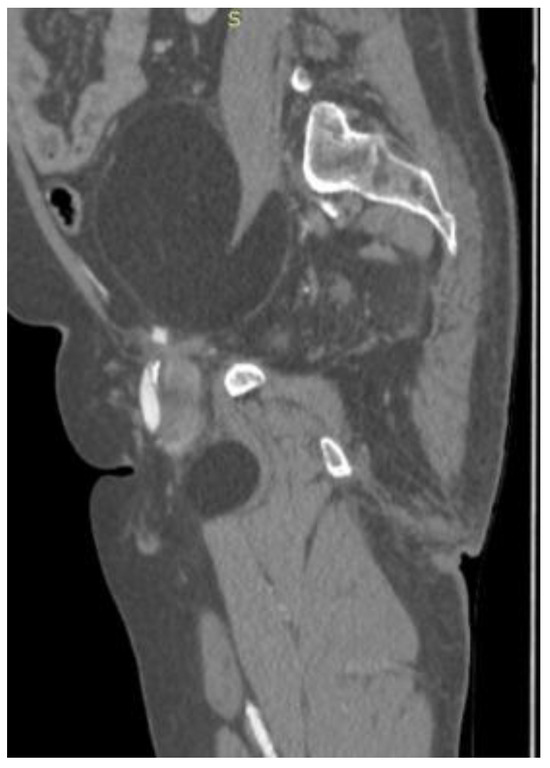

2. Case Presentation